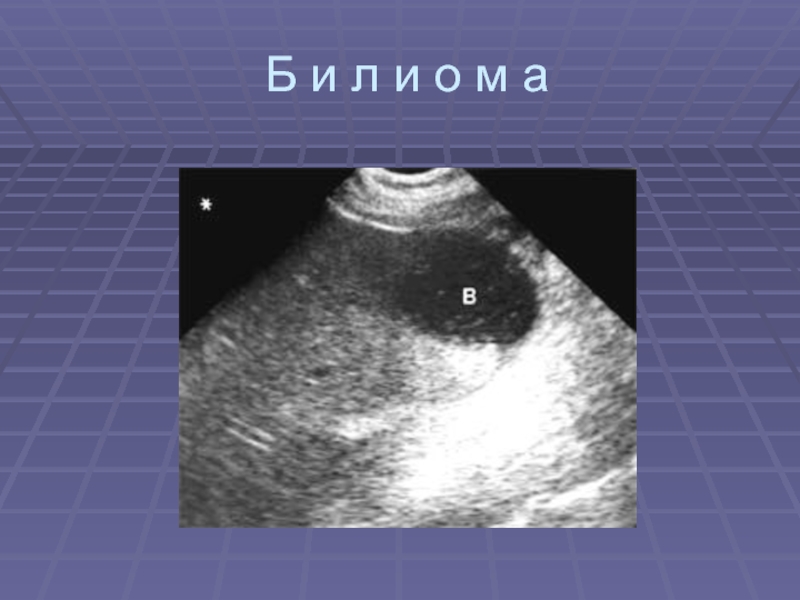

При несостоятельности швов – скопление относительно больших

количеств жидкости (желчи – билиома) под вентральной поверхностью печени, между

печенью и почкой, печенью и поджелудочной железой

Данные скопления осумкованы в большинстве случаев и не носят разлитого характера